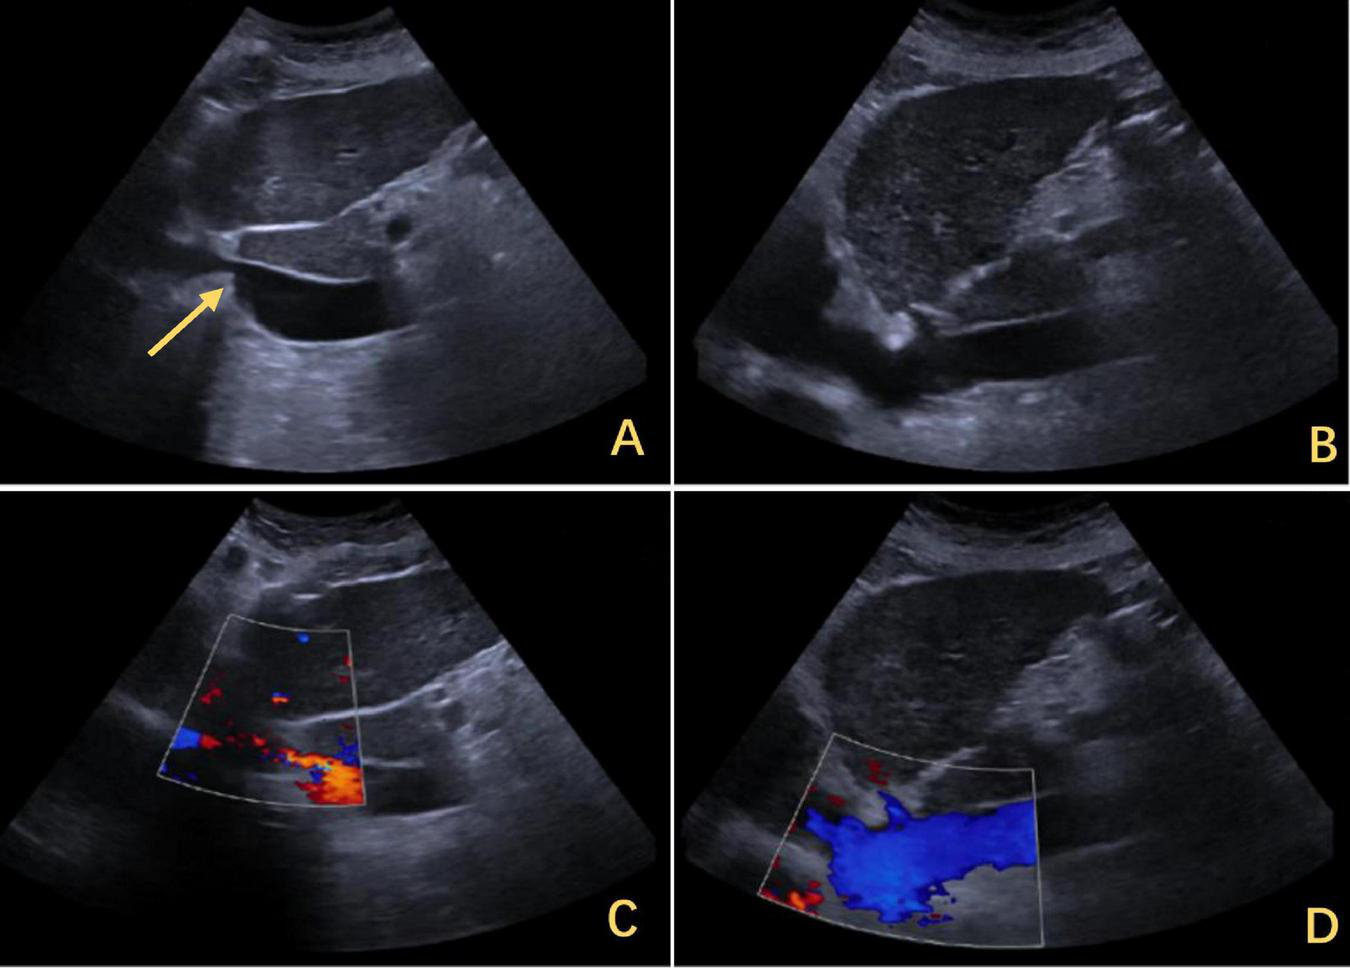

FIGURE 2

Ultrasound findings of IVC stenosis with outflow obstruction. (A) The IVC was approximately 0.33 cm wide, with its lower segment expanding to 2.8 cm. The arrows highlighted in yellow indicate stenosis. (C) The flow increased to 0.134 m per second. (B) After the release of the outflow tract obstruction after DP, the diameter of the IVC increased to 1.2 cm. (D) The flow rate returned to normal. IVC, inferior vena cava; DP, diaphragmatic plication.

The patient was a 72 years-old Chinese woman who was admitted with chronic abdominal pain lasting more than 30 years and recent reduced directionality lasting 2 weeks. A total of 15 days prior to presentation, she experienced blurred consciousness upon waking up in the morning. Cranial computed tomography (CT) imaging and magnetic resonance imaging (MRI) were performed at another hospital to exclude cerebrovascular disease and other abnormalities, and a scale-based assessment suggested disorientation. The patient’s blood ammonia level reached 90.2 μmol/L, while her liver and kidney function were normal. After treatment with oral lactulose and mentholated ornithine preparations, improvements in orientation and consciousness were observed. The patient had a history of type II diabetes mellitus and was taking metformin and glimepiride regularly, achieving good glycemic control. No other significant findings were noted in terms of family history, psychosocial history, or lifestyle history. On physical examination, the vital signs were normal, the skin and sclera were not yellowed, no mass was palpable in the upper abdomen, no tenderness was found in the abdomen, and Murphy’s sign was negative. After consulting our hospital, the following blood laboratory indices were measured: white blood cell (WBC) count, 3.69 × 109/L; hemoglobin (HBG), 105 g/L; alanine transaminase (ALT), 24.6 U/L; aspartate aminotransferase (AST), 43.9 U/L; and total bilirubin (TBIL), 33.7 mmol/L. Contrast-enhanced CT imaging revealed narrowing of the IVC above the HV confluence, cirrhosis, dilation of the main portal trunk to 13 mm, a tortuous splenic vein and esophagogastric fundic varices (Figure 1). Abdominal ultrasound revealed a constriction of the IVC (at the opening of the HV) approximately 0.33 cm in width, an increase in flow velocity to 134 cm per second (Figure 2C) and a dilatation of the IVC at its lower segment to 2.8 cm (Figure 2A). Combined with the patient’s CT and ultrasound assessment of IVC morphology, it was evident that the hepatic outflow tract was obstructed, thus confirming the diagnosis of BCS.

The right diaphragm dropped to almost the same level as the left diaphragm on the third day after DP (Figure 4B). The patency of the IVC stenosis was restored with by increasing the internal diameter to 1.2 cm (Figure 2B). And the flow rate returned to normal (Figure 2D). The patient’s blood ammonia level decreased to 66.4 μmol/L. She had a thoracic close drainage removed on the third postoperative day, had no postoperative complications, and was discharged on the fourth postoperative day. At 1 year postoperative follow-up, ultrasonographic evaluation of IVC revealed a maximum diameter of 1.46 cm, with a mean flow velocity of 0.5 m per second and peak velocity of approximately 1 m per second (Figure 7). Serial blood ammonia monitoring demonstrated persistently normal levels throughout the follow-up period (Figure 8).